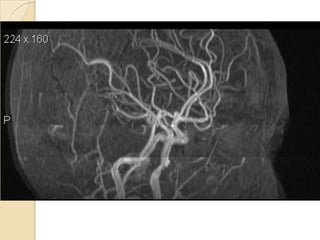

Arteries of the brain (lateral view) - MRA

1. Anterior cerebral artery

2. Anterior communicating artery

3. Basilar artery

4. branches (in insula) of middle cerebral artery

5. Cavernous portion of internal carotid artery

6. Cervical portion of internal carotid artery

7. Genu of middle cerebral artery

8. Intracranial (supraclinoid) internal carotid artery

9. Middle cerebral artery

10. Ophthalmic artery

11. Petrous portion of internal carotid artery

12. Posterior cerebral artery

13. Posterior cerebral artery in ambient cistern

14. posterior cerebral artery in interpeduncular

cistern

15. Posterior communicating artery

16. Posterior inf cerebellar artery.

17. Quadrigeminal portion of posterior cerebral

artery

18. Superior cerebellar artery

19. Vertebral artery